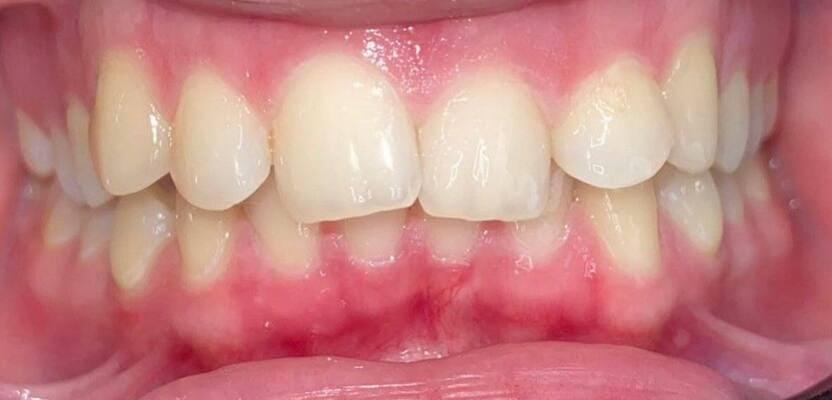

Дівчинка 7 років, перше вересня, гойдалка… Вивих постійного зуба: якщо в такій ситуації зволікати, дитина може втрати постійний зуб назавжди. Батькам порекомендували нас і пацієнти одразу приїхали. Через складність і травматичність процедур вирішено проводити лікування в анестезіологічному супроводі. Зуб поставлений на місце (репонований), проведена хірургічна обробка і ушивання рани губи. Останнє фото через рік після травми: зуб на місці і корінь продовжує розвиватись, губа повністю загоїлась